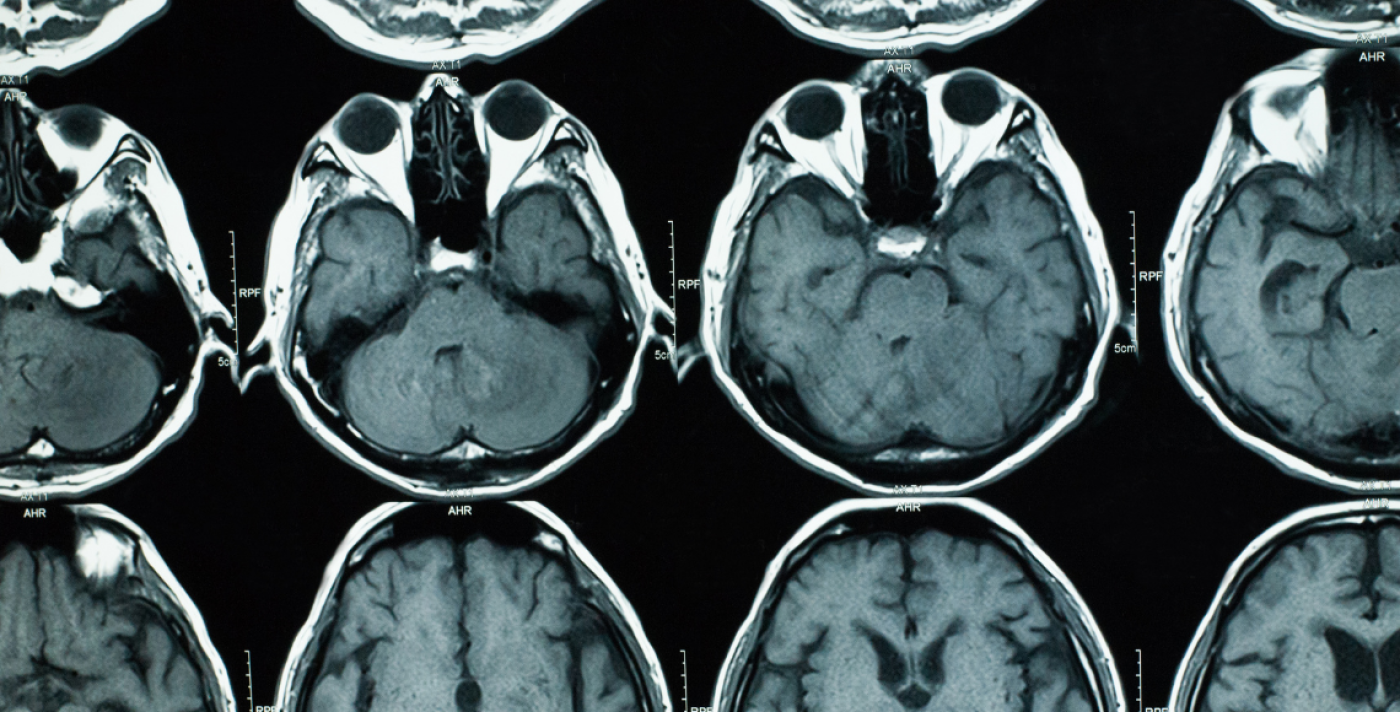

Brain imaging is a key tool in understanding the causes and development of psychiatric and neurological disorders.

Magnetic resonance (MR) is the most widely applied brain imaging technique. However, scanners are expensive (about £3 million for the machine) and require highly engineered buildings with appropriate magnetic shielding and expensive maintenance to cool the scanner hardware.

Our Biomedical Research Centre will support the validation of this technology. In order to ensure that ultra-low field is valid and reliable, we are using advanced artificial intelligence (AI) methods to improve image quality and calibrate the images against gold-standard high-field imaging. These AI methods are built on large databases of scans and models of brain structure. So far however this low-field scanner has only been tested on scans of healthy brains.

To make this low-cost technology clinically useful, we will harness the large datasets that already exist within the Biomedical Research Centre (representing multiple disorders and pathologies) and data from our NHS partner hospitals and show that the images produced are powerful enough to identify pathology and are valid and clinically reliable. We aim to develop these analysis techniques by adopting advanced statistical methods which have been tested in clinical groups.